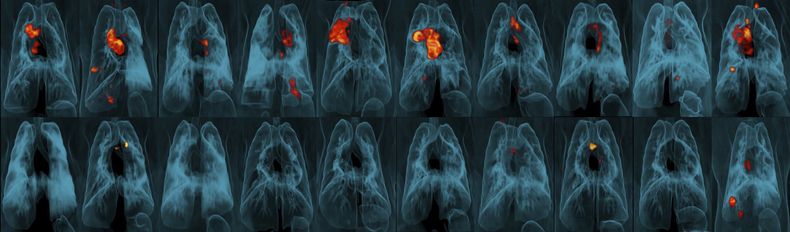

Seis meses después de las vacunaciones, los investigadores colocaron la bacteria de la tuberculosis directamente en los pulmones de los animales y observaron para ver si se infectaban. Los monos que recibieron la inyección subcutánea que se usa actualmente, incluso en una dosis más elevada, sólo estaban ligeramente más protegidos que los animales no vacunados, y el rocío tampoco fue muy efectivo.

Pero en 9 de cada 10 monos, una dosis de vacuna más elevada de lo usual inyectada a una vena funcionó mucho mejor, reportaron los investigadores en la revista Nature. El equipo no halló rastros de infección en seis de los animales y contabilizó niveles muy bajos de bacterias de la tuberculosis en los pulmones de tres.

¿A qué se debe? La hipótesis es que células inmunológicas clave llamadas linfocitos T tienen que llenar los pulmones para matar a las bacterias de tuberculosis, y pueden hacerlo con mayor rapidez cuando la vacuna es transportada rápidamente a través del torrente sanguíneo. Las pruebas mostraron linfocitos T más activos que permanecían en los pulmones de monos vacunados de la nueva forma.